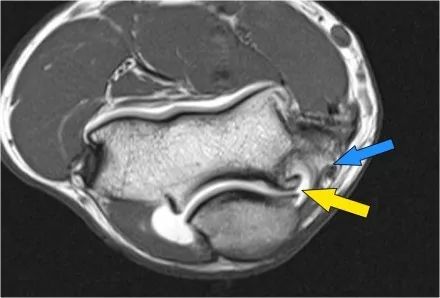

在研究韧带时,尤其是UCL,始终使用轴向图像。如果你看内侧上髁,你会发现后束是一个薄的结构(蓝色箭头)。注意在肘管内的尺神经。

后束形成肘管隧道的地板。支持带覆盖肘管。请注意,前束更厚(白色箭头)。您可以看到前韧带和后韧带之间的区别,即使它们形成一条韧带。走向远端,我们会看到它们合并在一起以附着于崇高的结节。

下面的图像,请注意,前束是完整的,并牢固地附着在崇高的结节上(黄色箭头)。在接下来的两张图像上,有一些软组织水肿,后面有更多异常信号(红色箭头)。所以我们怀疑后束的病理学。现在你记得轴向图像可能会有所帮助。

在下面轴向图像上,我们很好地看到前束是o.k. (红色箭头)。它旁边只有一些水肿。

然而,后束不是o.k,有一部分撕裂。这种情况我们偶尔会在投掷运动员中看到,前束完整,肘部不稳定。他们以某种方式撕裂了他们的后束,导致疼痛。他们不需要手术,但它仍然可能让他们在游戏中停留很长一段时间。